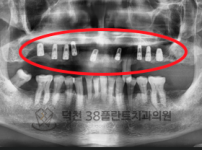

치료전후